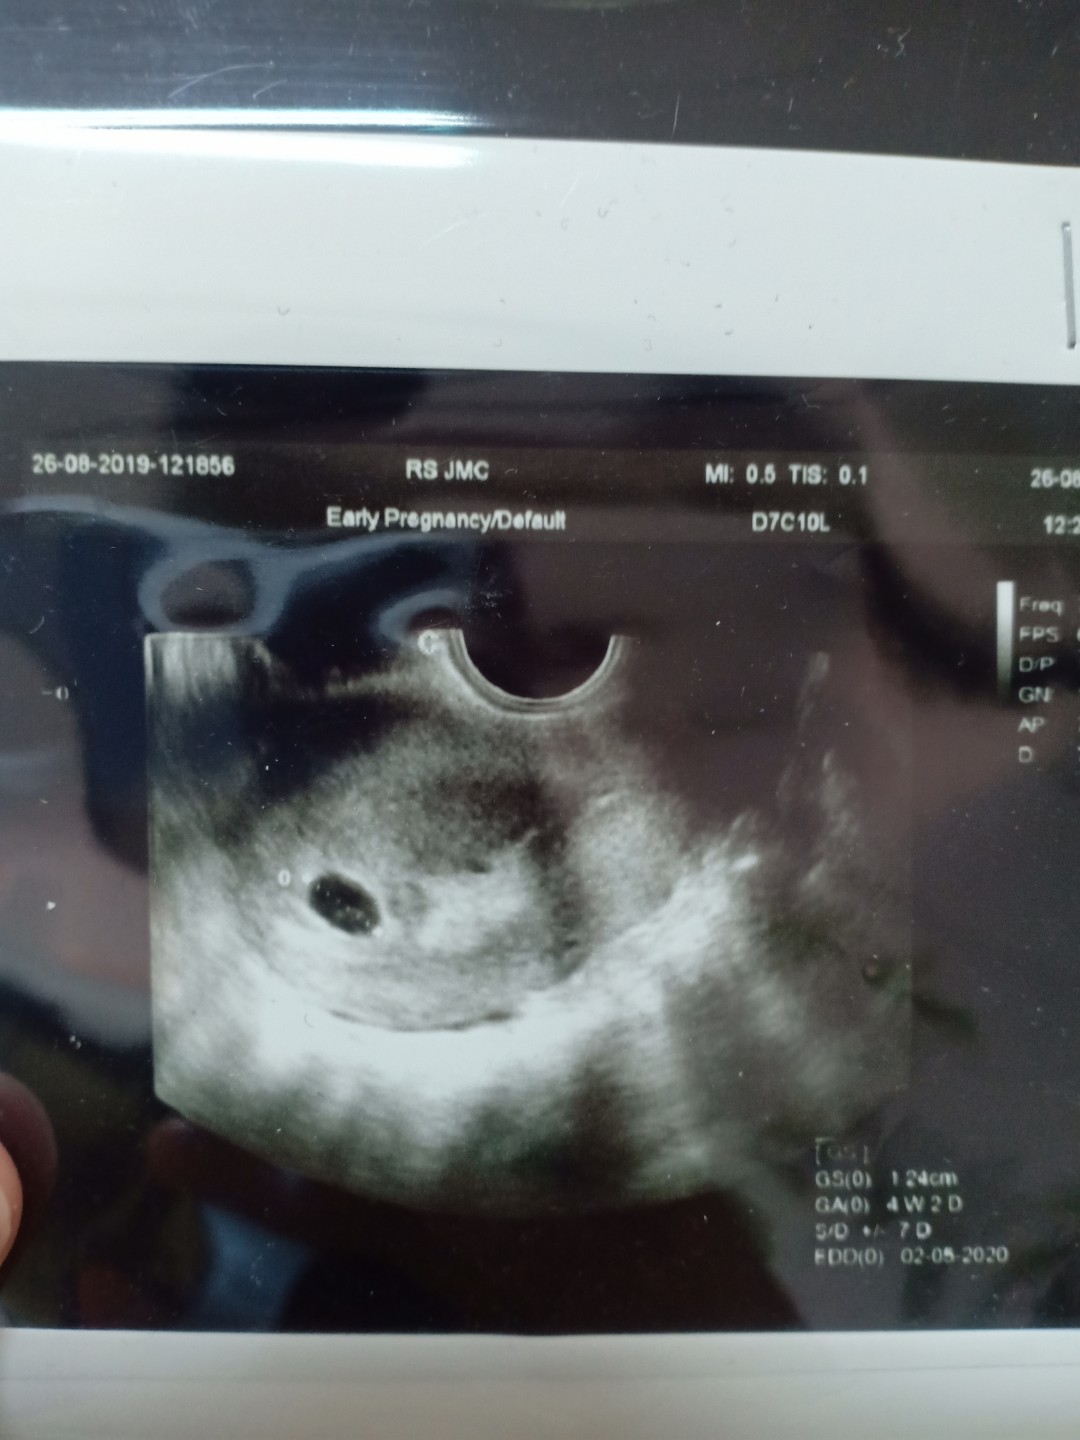

Bun,usia 6w gambar usg nya kygini normal ga sih Bun?? Tadi dokternya bilang, ga berkembang masa?? Disuruh balik lagi seminggu selanjutnya untuk di usg lagi

Sy 4 weeks ky gini bun, InshaAllah normal.

Normal bunda Sya dlu pas 6w jg msh kntong ukuran 2cm

Wajar 6 Minggu Bru keliatan kantungnya aja